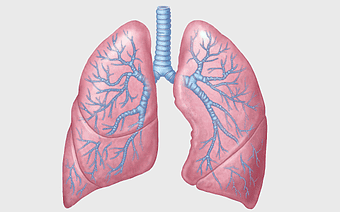

Lung Respiratory system, trachea and bronchus, pink lungs illustration, breathing anatomy, pulmonary health, respiratory function, medical education visuals -